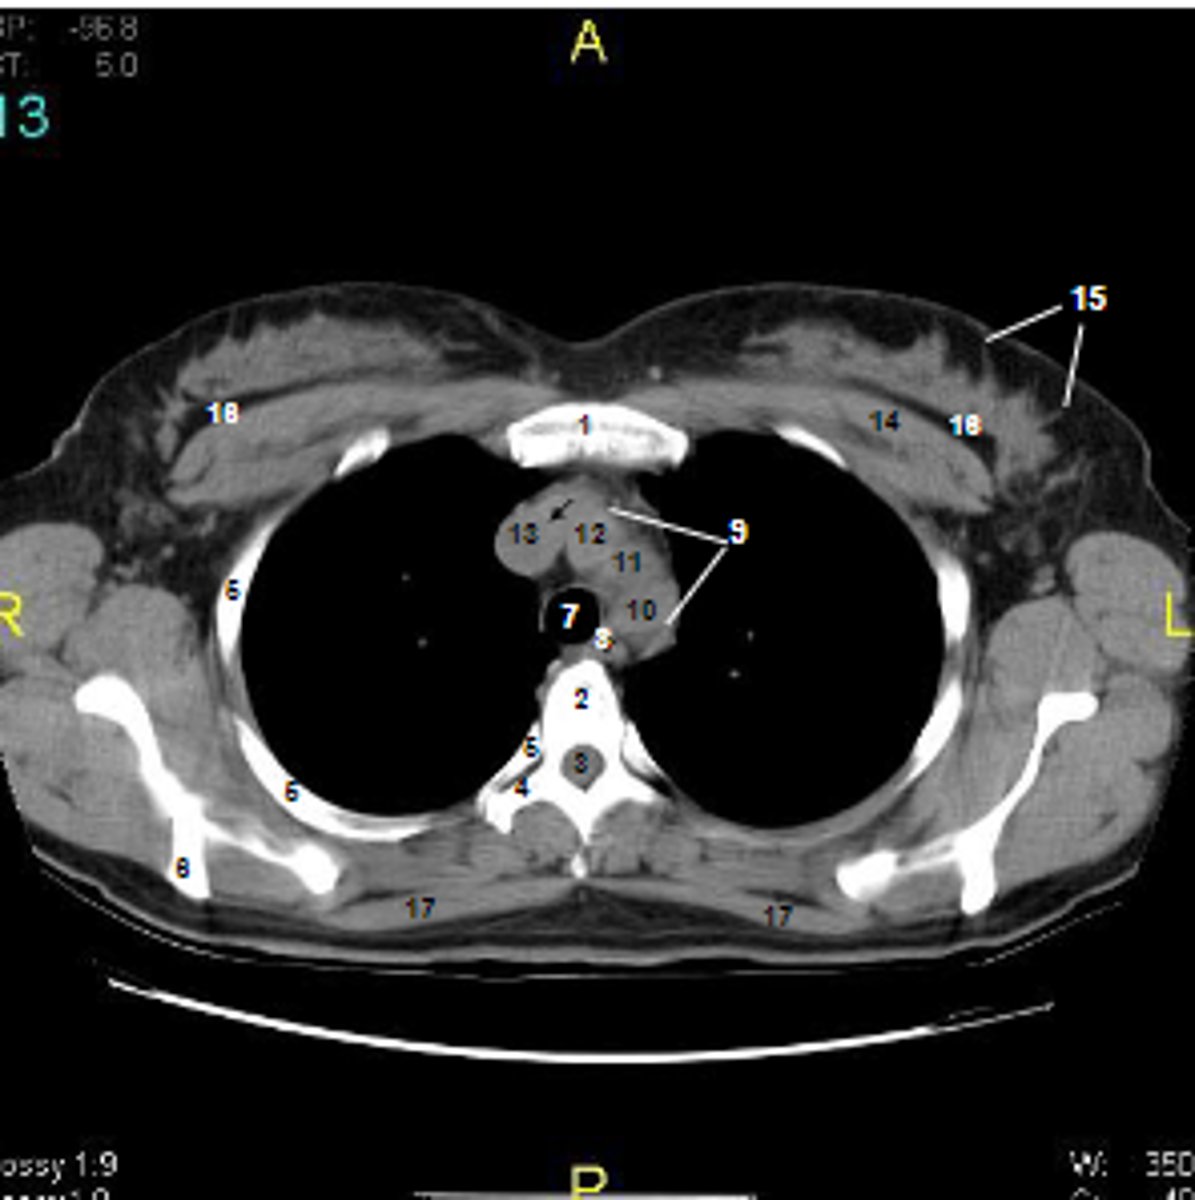

1

at what number is the sternum

2

at what number is the vertebral body

3

at what number is the vertebral canal/ spinal cord

4

at what number is the transverse process of vertebra

5

at what number is the rib

6

at what number is the spine of scapula

7

at what number is the trachea

8

at what number is the esophagus

9

at what number is the arch of aorta

10

at what number is the left subclavian artery

11

at what number is the common carotid artery

12

at what number is the brachiocephalic trunk

13

at what number is the superior vena cava

14

at what number is pectoralis major

15

at what number are Cooper's ligaments

16

at what number is the retromammary space

17

at what number is trapezius